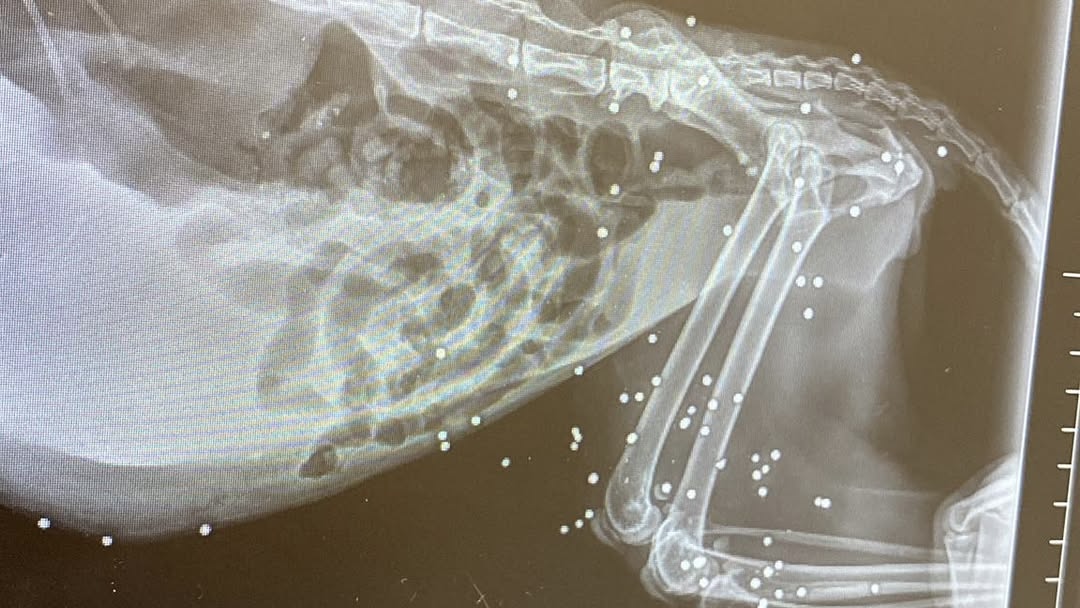

A soccorrerla sono stati i volontari che si occupano della colonia: insospettiti dalle sue condizioni, l’hanno immediatamente portata da un veterinario. L’esito della radiografia è stato scioccante: nel suo corpo erano conficcati ben 77 pallini.

A denunciare l’accaduto è la pagina Facebook “Animali smarriti Anzio & Nettuno”, che ha pubblicato un post destinato a scuotere le coscienze. La gatta, anziana e già affetta da gravi patologie tumorali, era stata recuperata per garantirle cure e dignità negli ultimi mesi di vita, non certo per la sterilizzazione, già effettuata in passato. «Tralasciando le masse tumorali – scrivono i volontari – questo è quello che l’essere umano riesce a fare. Piena di pallini».